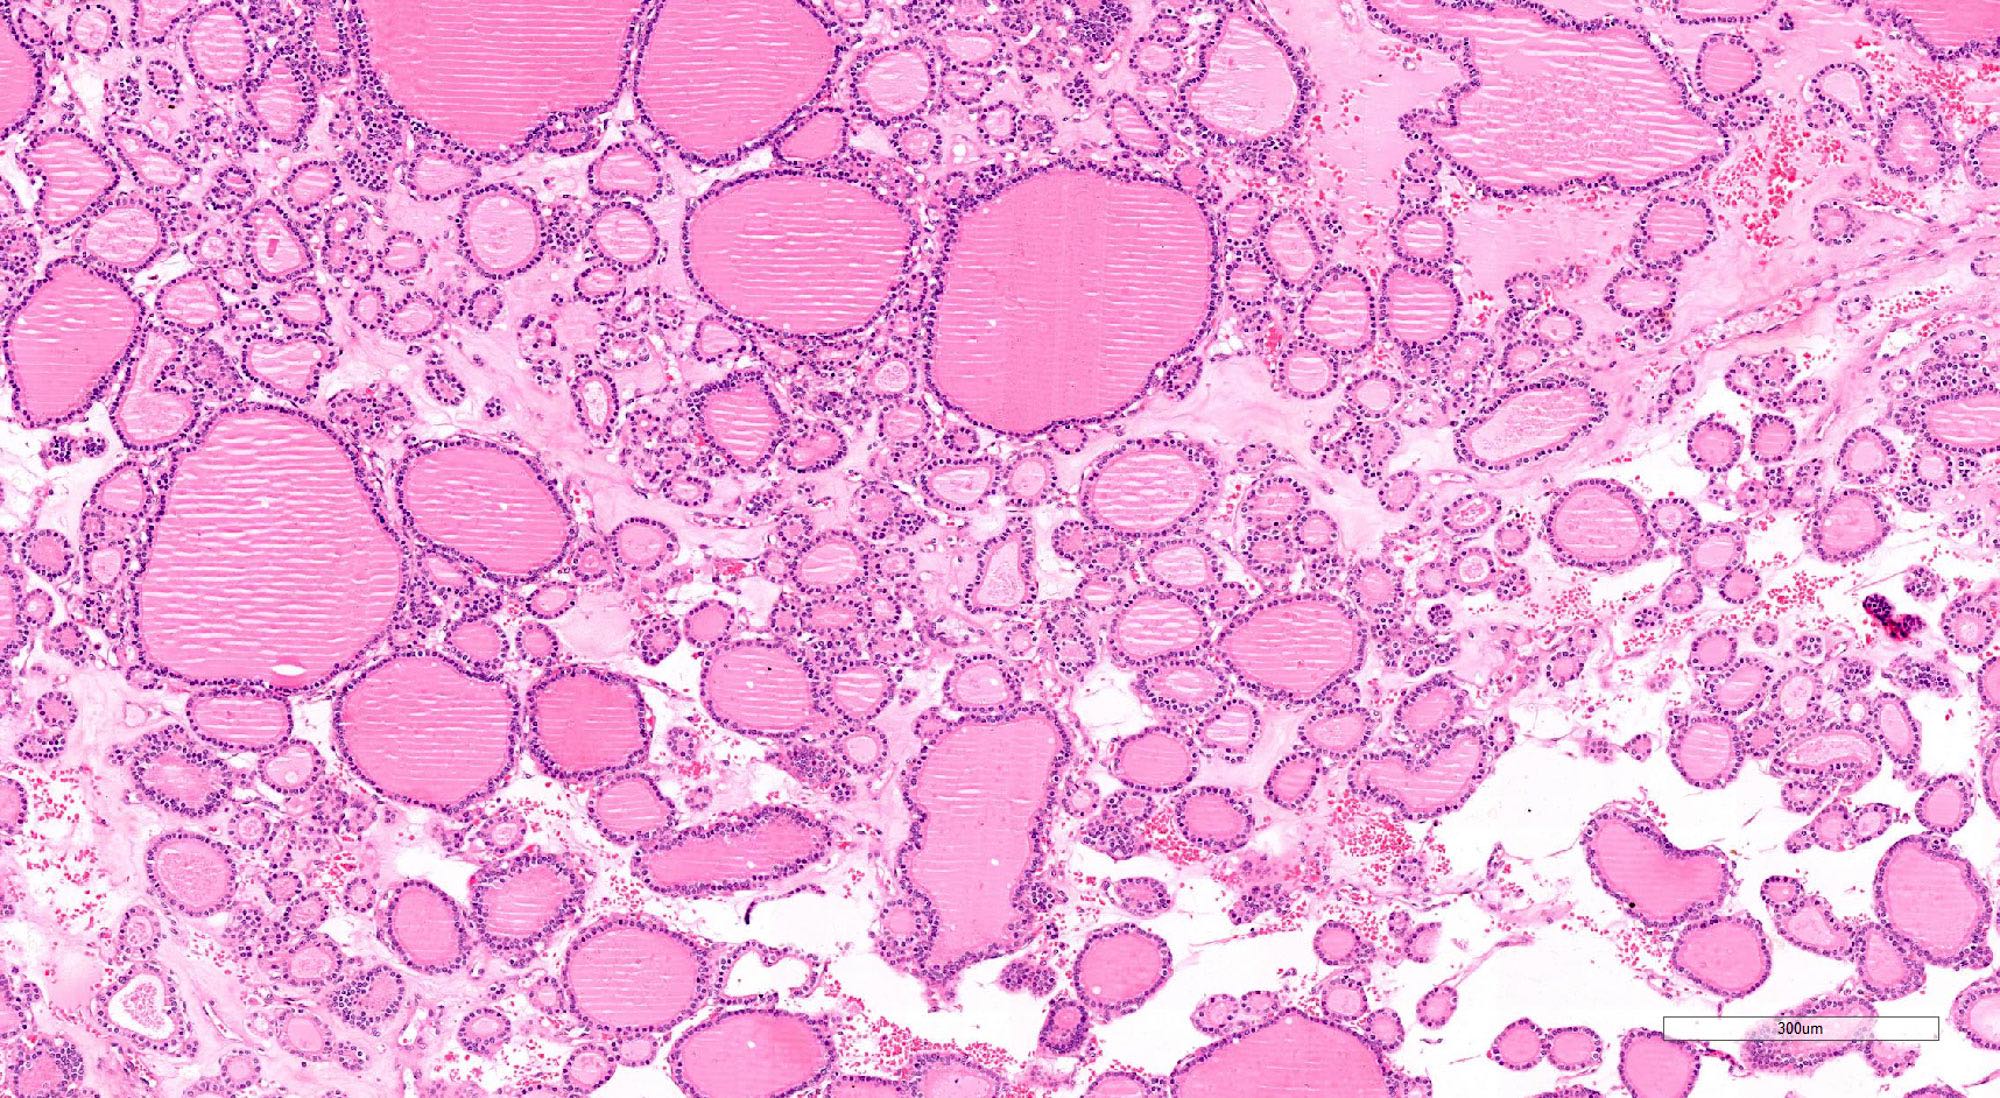

Microscopic (histologic) description

- Architecturally and cytologically different from surrounding gland

- Architectural patterns (can be seen in any combination)

- Normofollicular (simple): size similar to normal thyroid follicles

- Microfollicular (fetal): smaller follicles, small amount of intraluminal colloid

- Macrofollicular (colloid): large follicles, flattened epithelium, abundant colloid

- Cuboidal to low columnar cells

- Small round nuclei, smooth nuclear boundary, uniformly hyperchromatic or euchromatic, dense chromatin, absent nuclear features of papillary thyroid carcinoma, nuclear score 0 or 1 (JAMA Oncol 2016;2:1023)

- Inconspicuous nucleoli

- Mitoses are uncommon

- Scant stroma

Microscopic (histologic) images

Contributed by Shipra Agarwal, M.D., Andrey Bychkov, M.D., Ph.D., Mark R. Wick, M.D., Asmaa Gaber Abdou, M.D. and AFIP

Patterns: